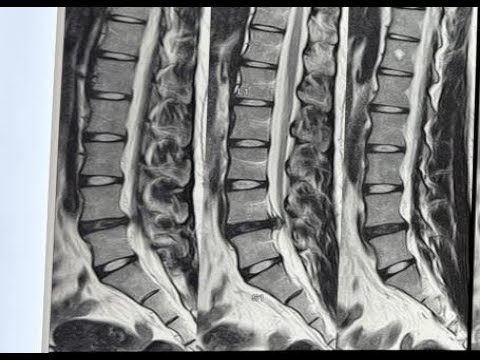

Hellow guys, Welcome to my website, and you are watching D11 D12 NEUROFIBROMA-DR LAXMIKANT BHOPLE/DR SANDEEP GORE SHREE GANGA HOSPITAL NANDED. and this vIdeo is uploaded by Dr. Laxmikant Bhople NeuroCare at 2024-07-24T04:56:42-07:00. We are pramote this video only for entertainment and educational perpose only. So, I hop you like our website.